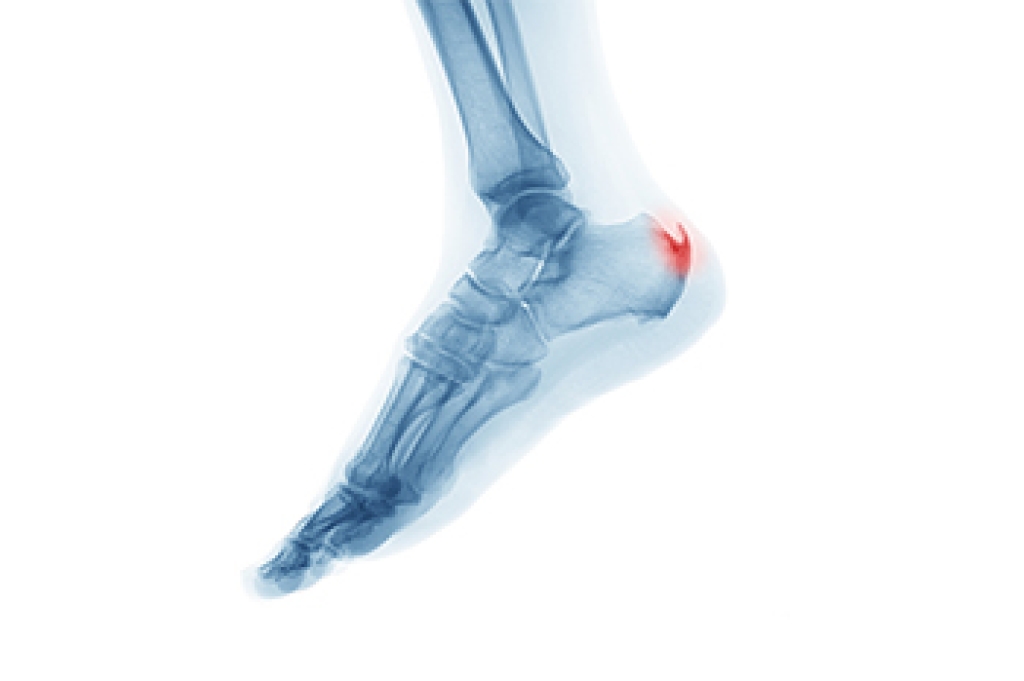

Plantar fasciitis is a common condition that causes pain in the heel and bottom of the foot. The primary cause of plantar fasciitis is repeated stress or strain on the fascia, often due to excessive walking, running, or standing. Other factors like wearing poor footwear, tight calf muscles, or being overweight can also contribute. The most noticeable symptom is sharp pain in the heel, especially when taking the first steps in the morning or after periods of rest. As the day progresses, the pain may lessen but can return with prolonged standing or walking. Diagnosis typically involves a physical examination where a podiatrist may palpate the heel and foot, and sometimes imaging tests to rule out other conditions. If you have heel pain, it is suggested that you contact a podiatrist who can accurately diagnose and treat plantar fasciitis.